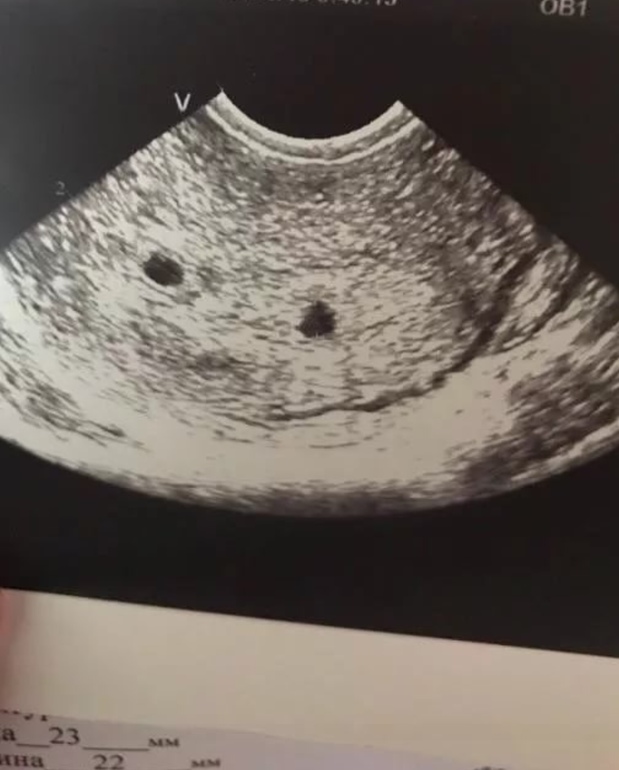

Узи,10 дней задержки

До последнего думала, что начнутся месячные, но нет, вот такое счастье меня настигло неожиданно.

Спустя 7 месяцев после ЗБ увидела || , но теперь другие страхи....